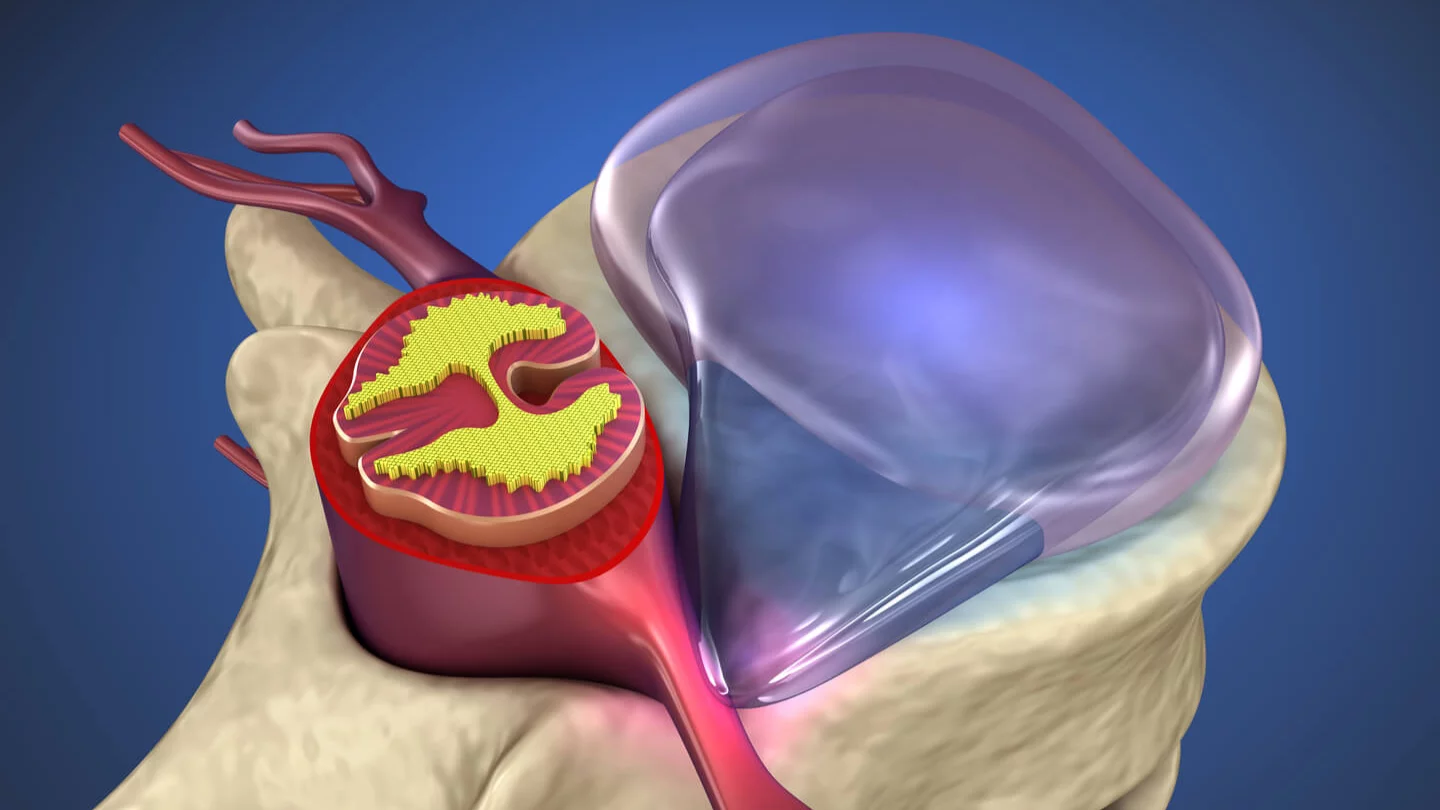

КТ-протрузии дисков: Визуализация и классификация